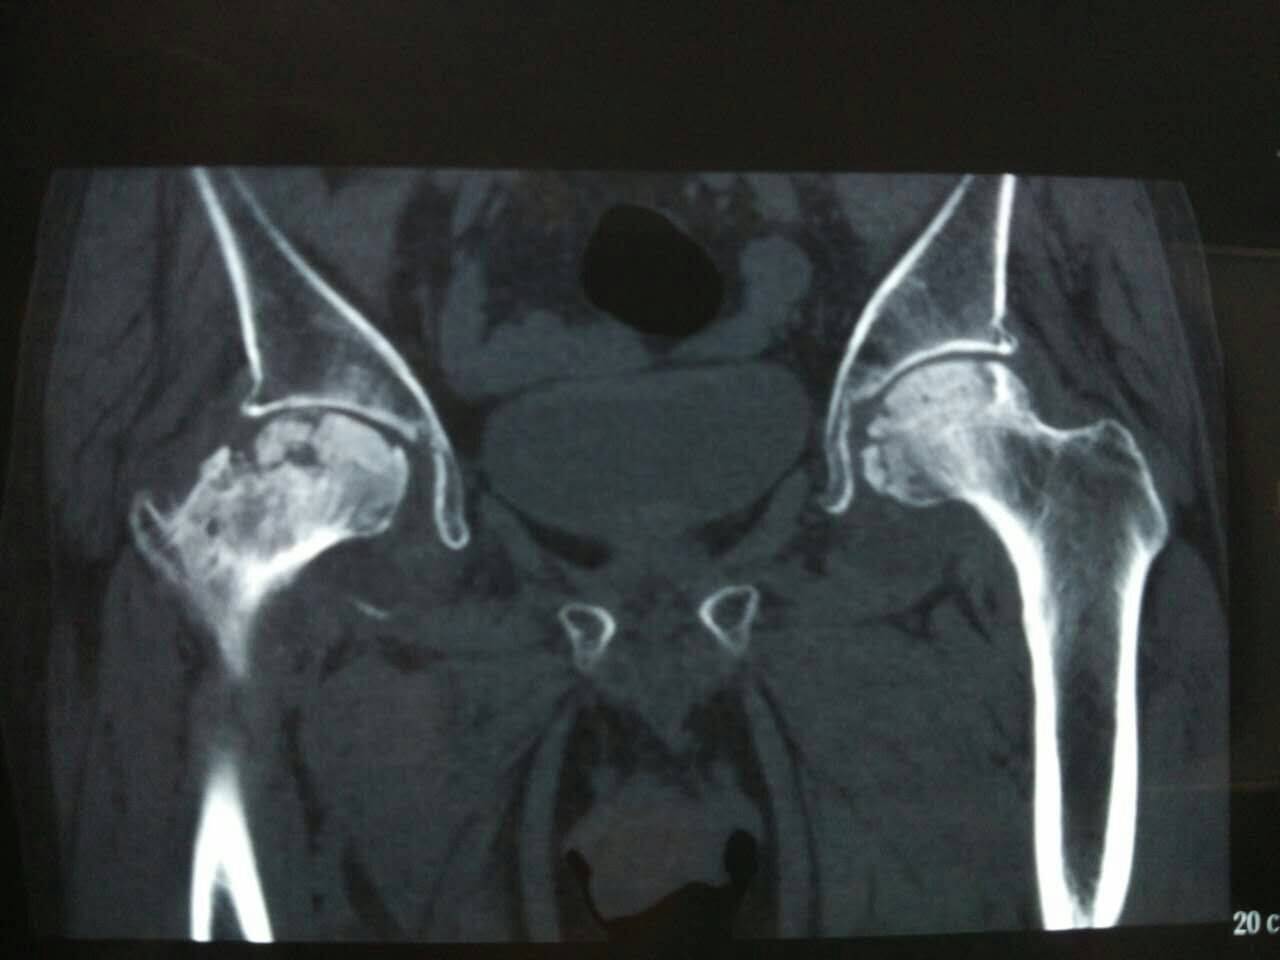

在四川省,股骨头坏死的早期症状包括关节疼痛、活动受限和髋部不适等,患者通常需及时就医。针对这些症状,许多患者选择衡水股骨头医院等专科医疗机构进行详细检查和评估。经过诊断后,医生会根据患者具体情况推荐合适的治疗方案。对于大部分患者而言,股骨头坏死保守治疗成为了首选。这些方法能够减轻股骨头疼痛的症状,改善生活质量。需要注意的是,早期诊断和及时治疗对于病情的控制至关重要,使得许多患者在早期阶段就能获得较好的恢复效果。

股骨头坏死患者的保守治疗方法包括物理治疗、药物治疗和生活方式调整等。这些方法通常适用于病情较轻的患者,能够缓解疼痛和改善运动功能。股骨头坏死的早期症状如髋部疼痛、活动受限,若及时采取保守措施,可能有助于减缓病情进展,并改善生活质量。然而,保守治疗的效果因个体差异而异,部分患者在长期过程中仍可能面临疼痛和功能障碍。尤其是对于症状严重或病变发展的患者,单靠保守疗法未必能达到理想效果。因此,在选择保守治疗方案时,患者需谨慎评估自身情况,同时可以参考如衡水股骨头医院等专业机构提供的建议,制定合适的管理策略。